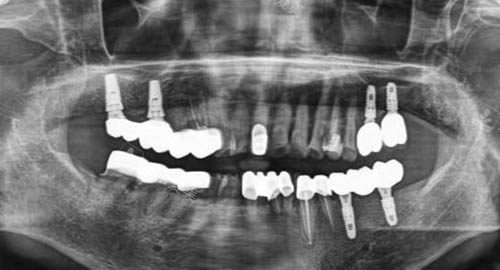

多颗牙齿种植ct

三、玖紫口腔在看牙种牙方面靠谱吗?

玖紫口腔在看牙种牙方面是非常靠谱的。

诊所拥有一支正规的医疗团队,医生们都具备丰富的临床经验和扎实的正规知识。

他们不断学习和更新技术,以确保能够为患者提供较靠前、较有效的治疗方案。

在设备方面,玖紫口腔引进了国内外靠前的口腔治疗设备,如智能化牙片机、种植牙系统等,这些设备能够提高诊断的更准性和治疗的结果。